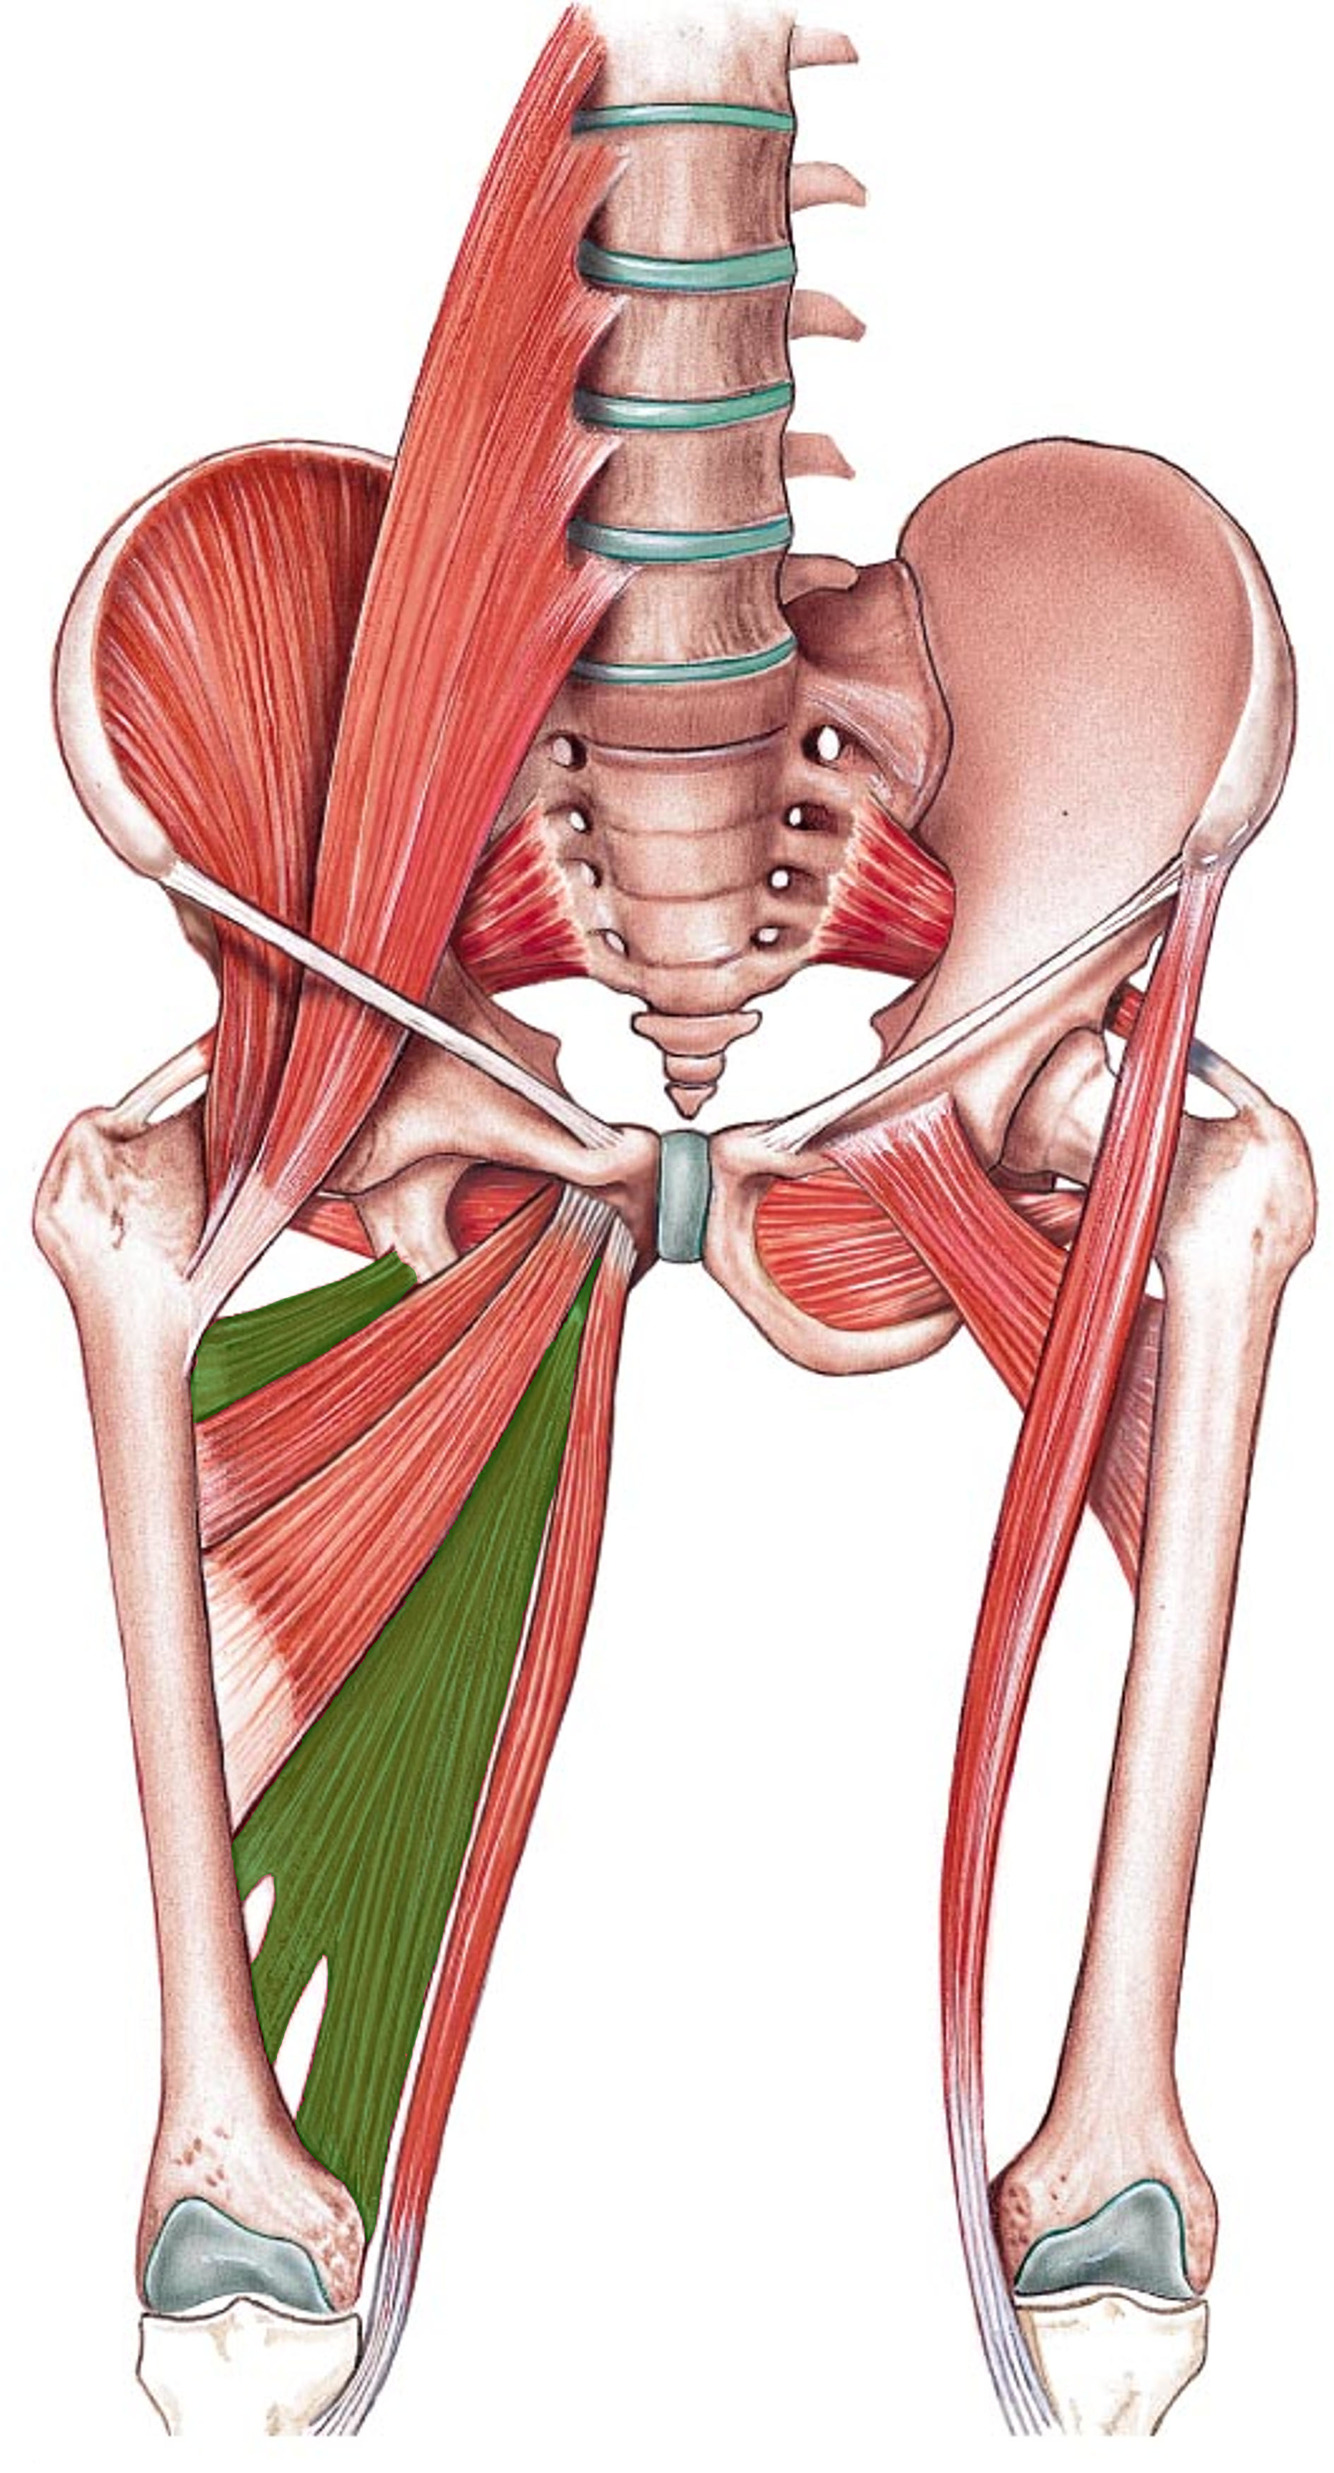

What is the innervation of this muscle (nerve roots)?

Muscle - Obturator internus

L5 + S1

What is the innervation of this muscle (nerve roots)?

Muscle - Superior gemelli

L5 + S1